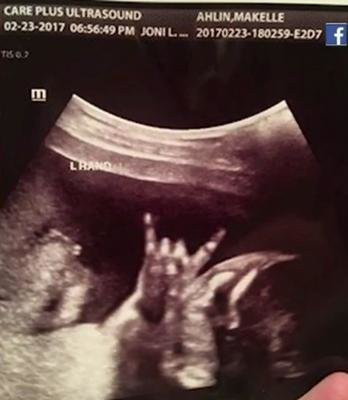

Bebeğin yanında bir de kedi bekliyorlar - Resim: 3

Zafer pozu.